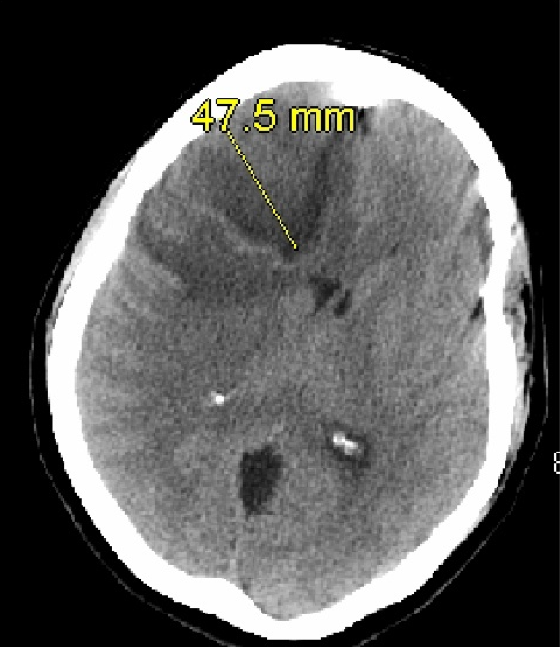

Diagnostic tests. Laboratory results were significant for an elevated white blood cell count of 19,700/µL with a neutrophil shift of 86%. A CT scan of the head without contrast showed a large lesion measuring up to 4.8 cm within the right frontal lobe with an apparent cystic component (Figure 1).

Figure 1. CT of the head without contrast showing a lesion with possible central cystic component measuring up to 4.8 cm in largest diameter.